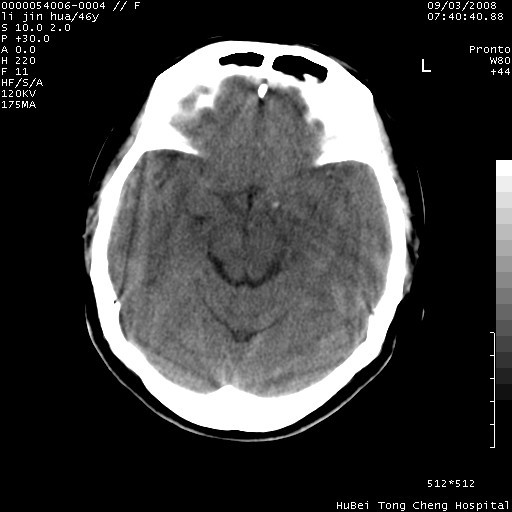

以下是引用panyishengct在2008-9-6 1:47:00的发言:[br]病史?[br]左侧枕/顶叶见一等/低混杂密度占位,壁完整,厚薄较均匀,其前方似有一类似小病灶,周围有水肿带,请结合病史考虑,脓肿可能,不排外转移瘤或胶质瘤,建议增强扫描。

以下是引用代课学生在2008-9-6 9:39:00的发言:[br]在无病史资料的情况下,脑脓肿、脑转移瘤、胶质瘤都有可能。还是先了解一下病史吧。